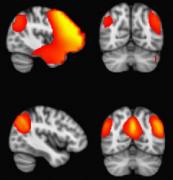

我们在加拿大多伦多大学儿童医院(SickKids)引入了脑磁图(MEG)指导的难治性局灶性癫痫儿童癫痫手术。顽固性局灶性 癫痫患儿 的手术候选资格和手术程...